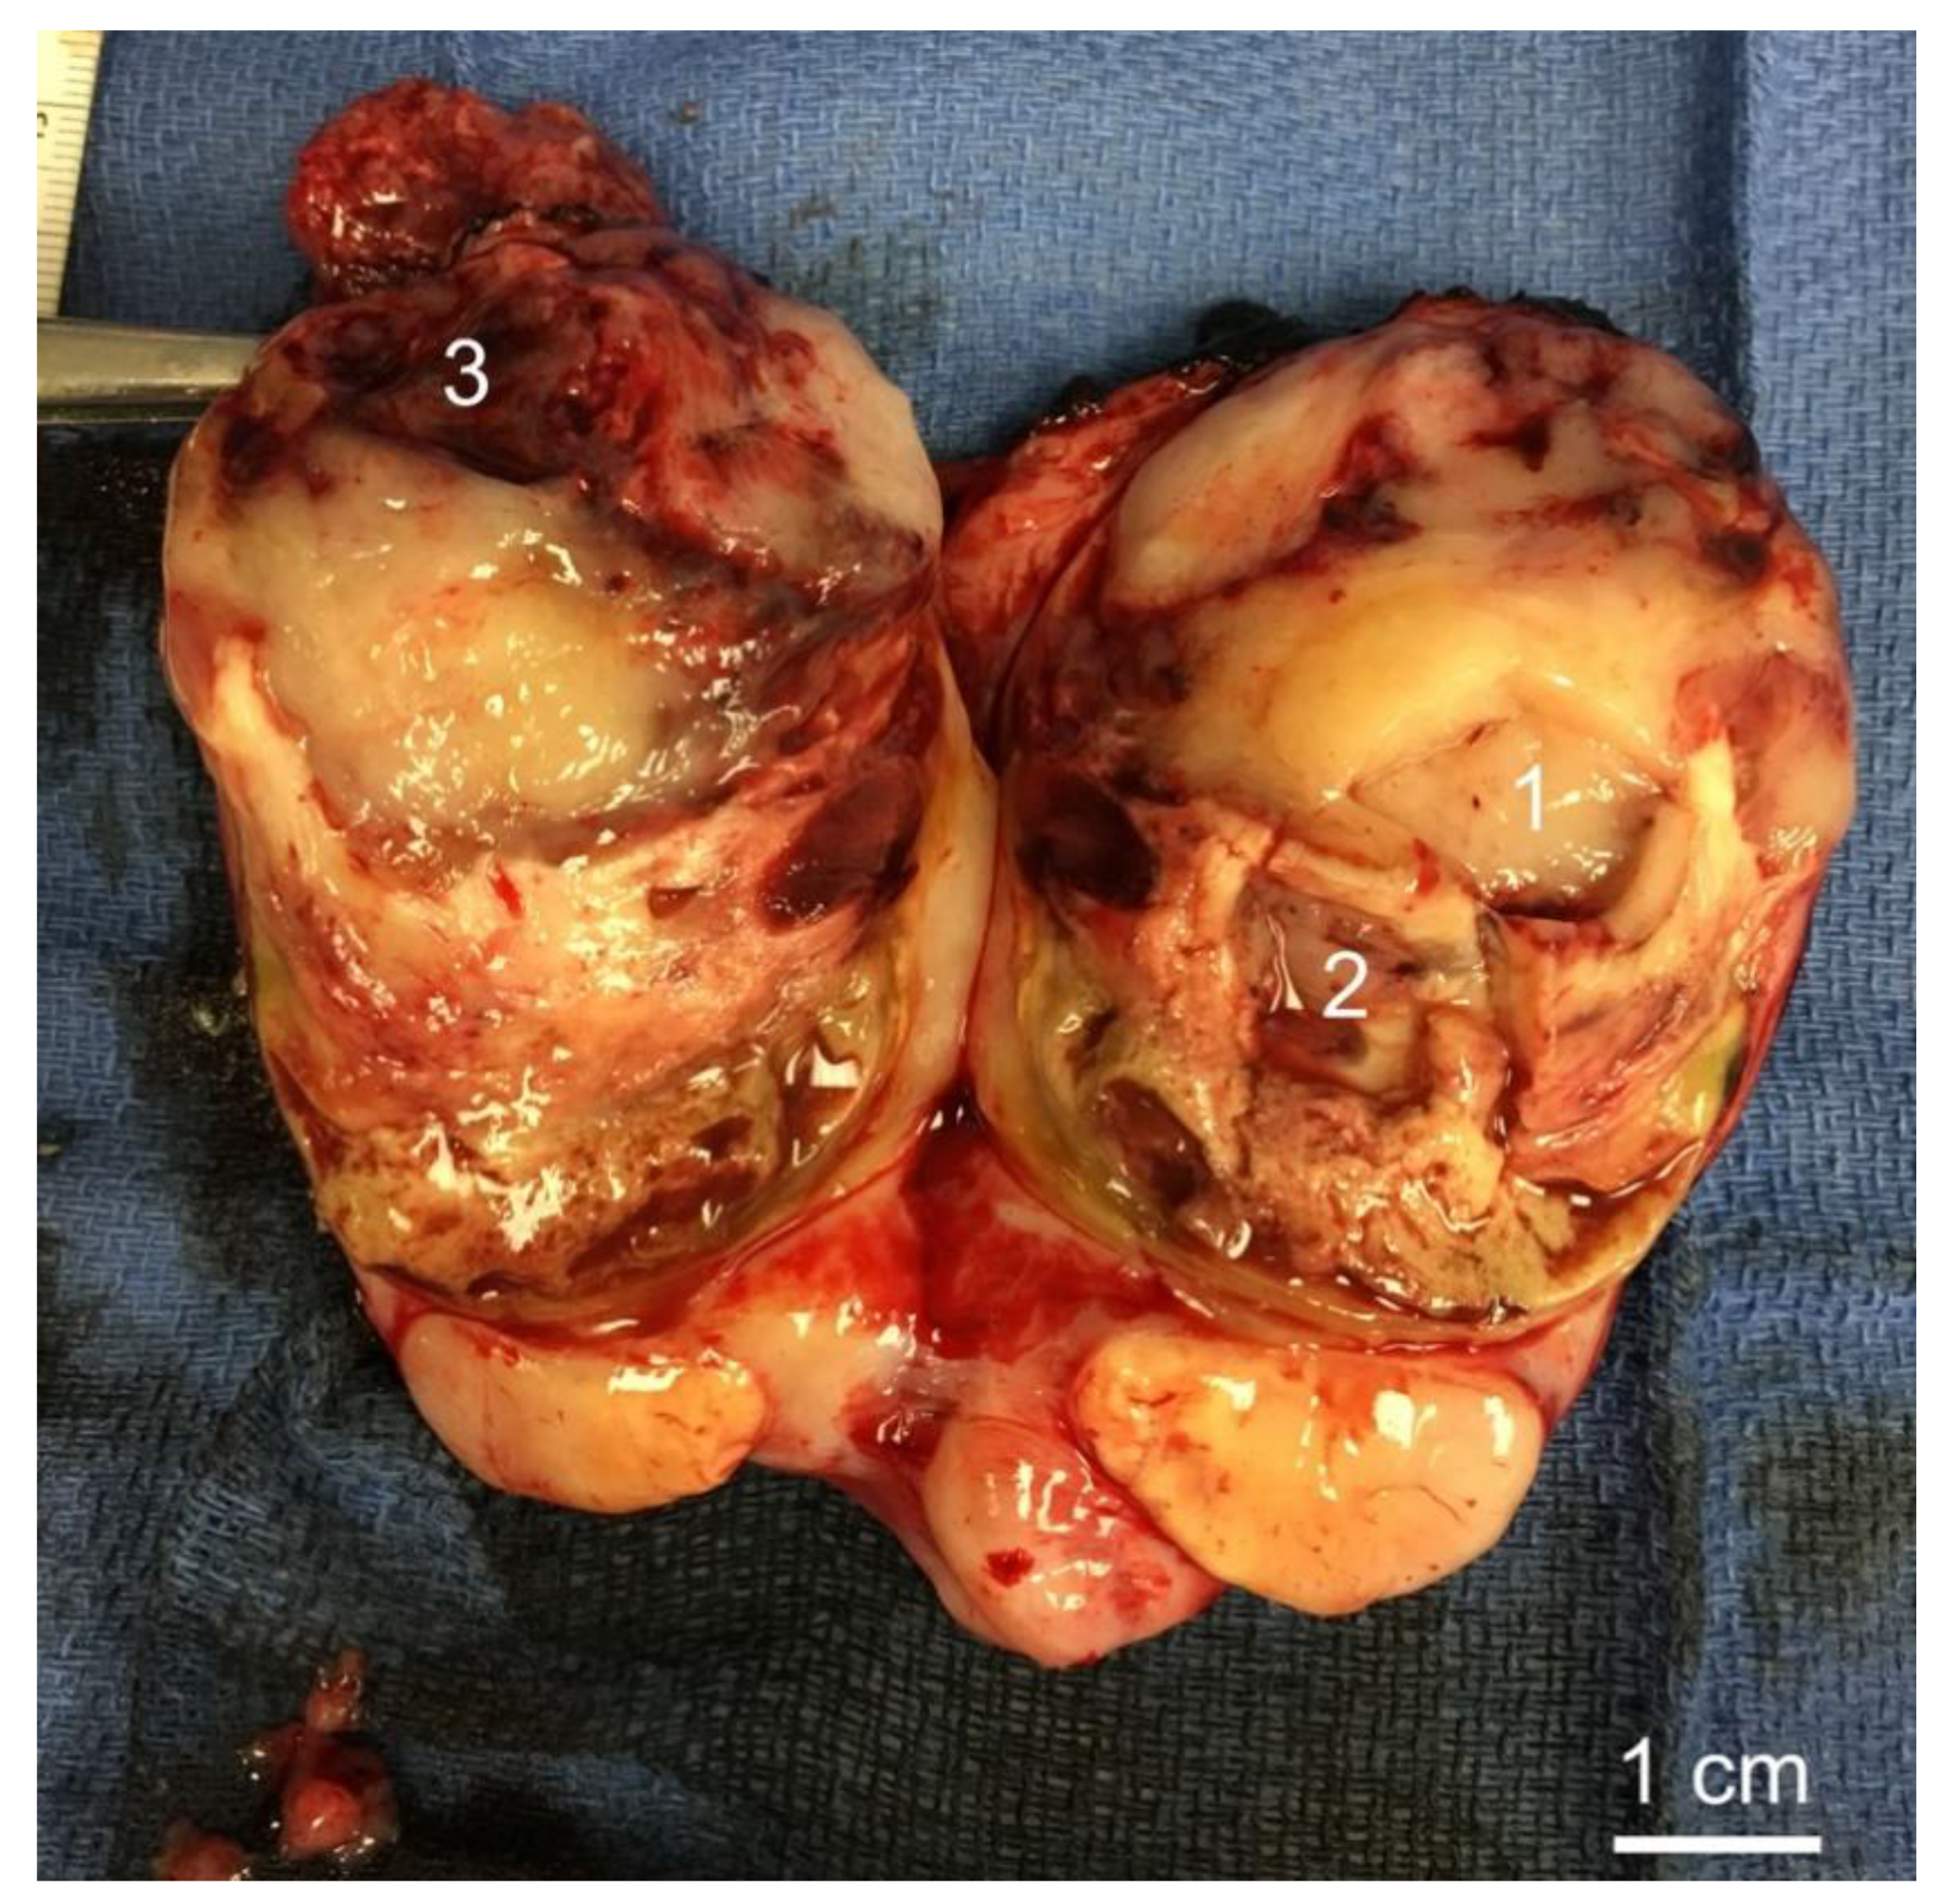

3.2. Histology of Biopsy Sites